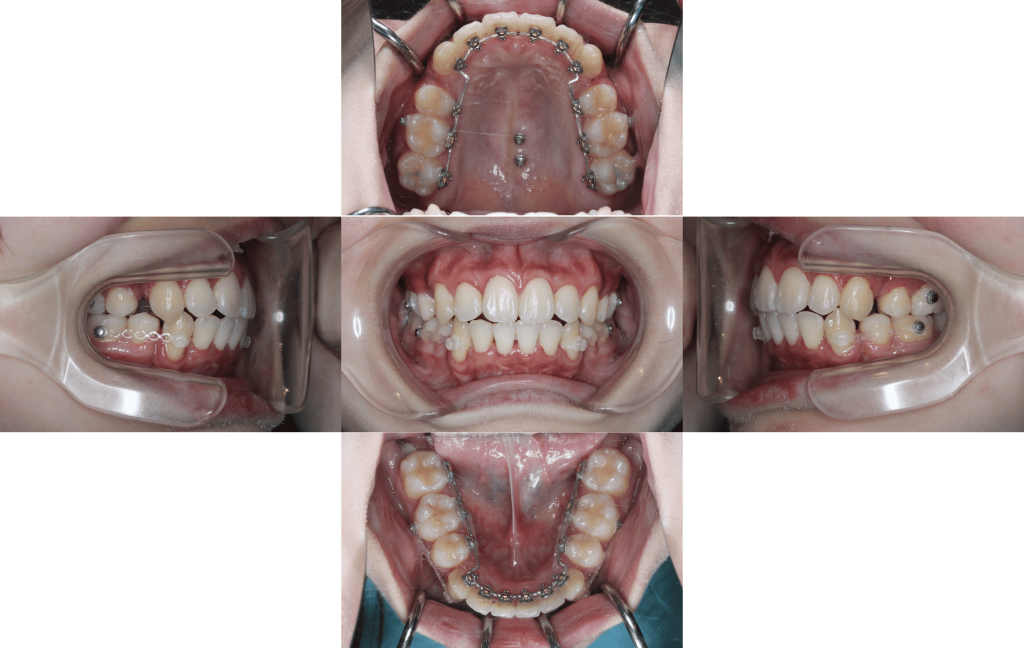

約1年経過

約1年6か月後